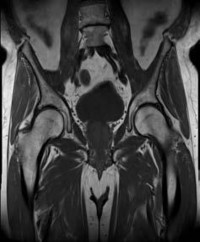

Question 2

A 75-year-old woman sustains a displaced femoral neck fracture after a mechanical fall. Which of the following is the predominant blood supply to the femoral head that is at risk of disruption in this injury?

Explanation

The predominant blood supply to the adult femoral head is provided by the lateral epiphyseal artery, which is the terminal branch of the medial femoral circumflex artery (MFCA). This runs along the posterosuperior aspect of the femoral neck and is frequently disrupted in displaced femoral neck fractures, leading to a high risk of avascular necrosis.